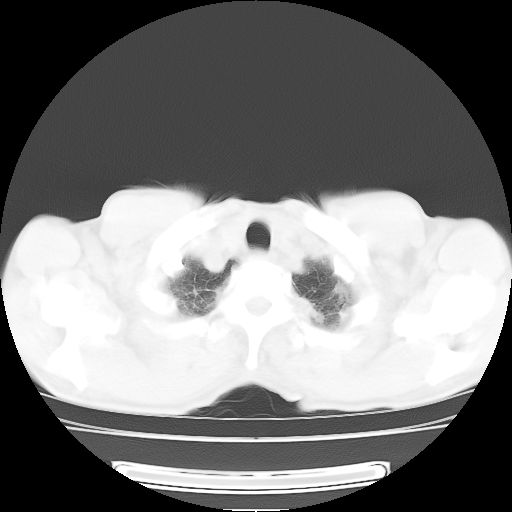

标题: CT25795:感冒后反复咳嗽两月余,痰中带血半月余。X诊断“肺 [打印本页]

标题: CT25795:感冒后反复咳嗽两月余,痰中带血半月余。X诊断“肺

1.双肺肺梗塞(理由:病灶呈三角形,与胸膜相连且局部胸膜肥厚,左心室增大)伴肺感染。

肺梗塞虽然有创意,但不现实。我考虑感染性病灶。

考虑两肺感染性病变,左肺上叶舌段肿瘤性病变待排;建议抗炎治疗后复查。